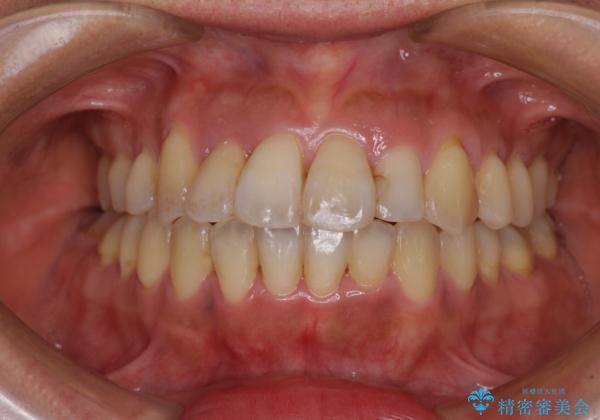

狭い上顎骨を拡大 著しい叢生を抜歯矯正で改善

- 上顎の著しい叢生と奥歯の咬みにくさを気にして来院された患者様です。

骨格的に上顎は狭く、下顎は右側にシフトしていたため、右側臼歯はクロスバイトとなっていました。

上顎骨を急速拡大装置により拡大し、ワイヤー装置による抜歯矯正治療を行うこととしました。